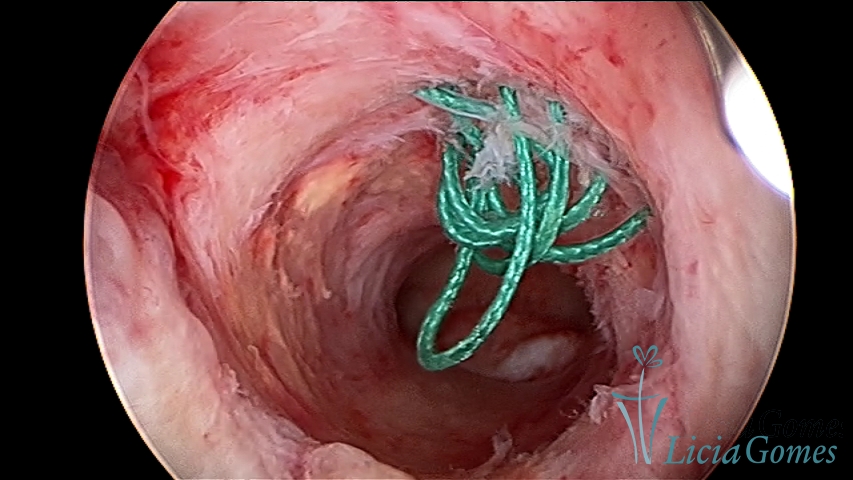

Retraction of a cesarean section scar with a non-absorbable suture for 30 years.

Retraction of a cesarean section scar with a non-absorbed suture, as a foreign body

×